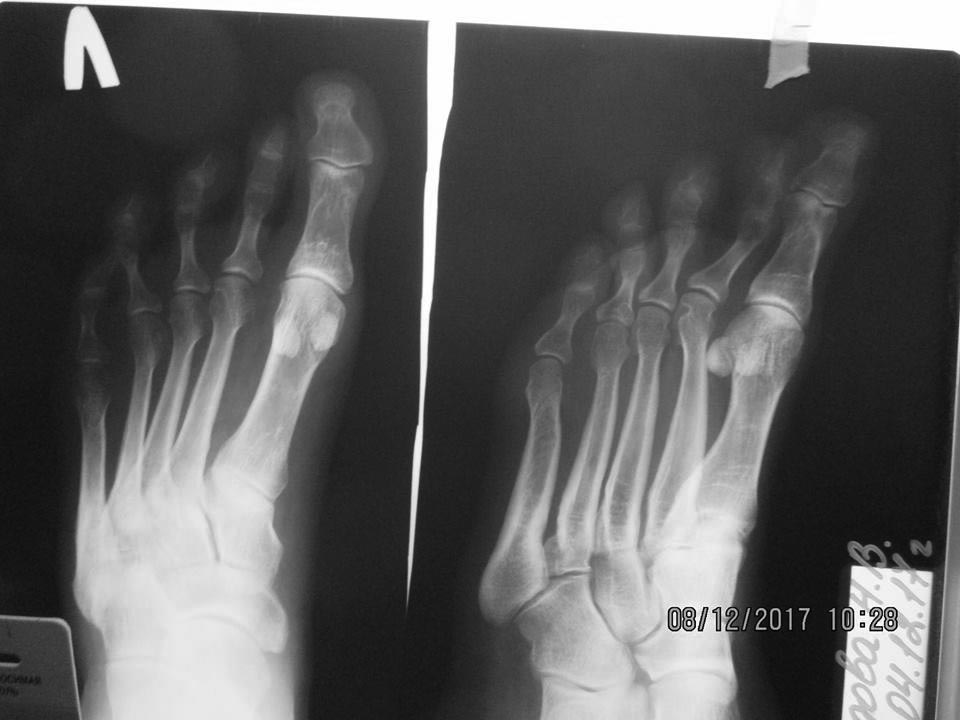

Пациентка 36 лет, несколько избыточного веса. За неделю до обращения почувствовала боль в правой стопе. В 2015 была аналогичная ситуация, тогда болевой синдром продолжался в течение 3-х месяцев. Местно: на тыльной поверхности переднего отдела - отёк, гиперемия и боль при пальпации; форма стоп – обычная. На рентгенограмме: перелом дистальной трети III-ей плюсневой кости со смещением, консолидированный перелом проксимальной трети IV-ой (V-ой?) плюсневой кости, дугообразная деформация III-V-ых плюсневых костей. От госпитализации отказалась. Наложена гипсовая лонгета, рекомендовано обратиться к эндокринологу (остеопороз?). Через 1,5 мес. – сращение перелома (рентгенография левой стопы – без особенностей). Лабораторное исследование у эндокринолога пока не выявило какой-либо патологии (УЗИ щитовидной и паращитовидных желез – 15.01.18).Три «незаметных» перелома! Что Вы думаете, господа, по этому поводу?

Интересная рентгенологическая картина! Стрессовые переломы различной давности... И все с одной стороны.